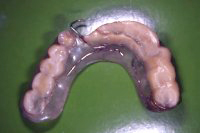

Ein 79 Jahre alter Mann wünschte sich auf den 80igsten Geburtstag, wieder mal richtig in ein Steak beissen zu können. Die Gebissituation war sehr ungünstig (Abb. 1) und so unangenehm, dass er zum Essen eine Aufbissschiene im Oberkiefer tragen musste (Abb. 2, 3), ansonsten er sich mit seinem eigenen oberen Eckzahn bei Kieferschluss in das Unterkieferzahnfleisch gebissen hätte(Abb. 4).

Im Unterkiefer habe ich einige parodontal schwer geschädigte Zähne gezogen und zwei Monate später sieben Implantate gesetzt, wobei bei einigen kleinere Augmentationen gemacht wurden (advanced implantology). Nach sechswöchiger Einheilung der Implantate (Abb. 5 und 6) wurden die Aufbauten in die Implantate eingeschraubt und die verschiedenen Brücken festsitzend zementiert.

Abb. 7 zeigt das Resultat im Unterkiefer nach der Sanierung. Im Oberkiefer läuft dieser Fall unter komplexer Implantologie als Fall 8 weiter.